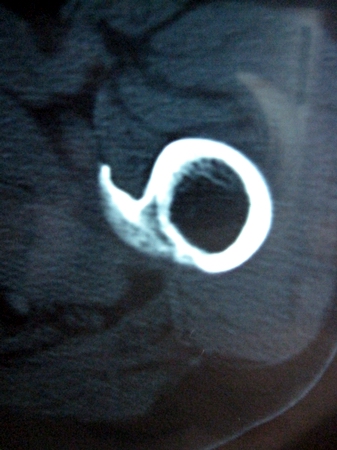

以下是引用lkc8963在2008-12-19 21:19:00的发言:[br]左?右?患侧大转子上移,股骨颈骨质浓杂,髋周见多发条片状骨化影,以小转子为著,多为陈旧性股骨颈骨折后改变并骨化性肌炎.请咨询既往史!